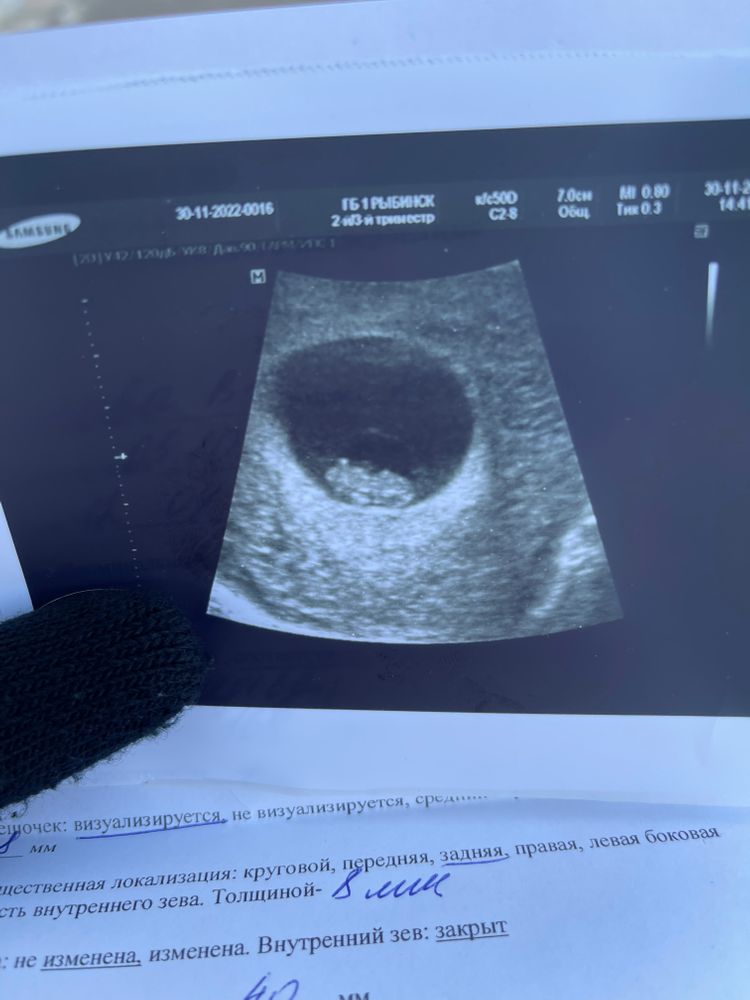

Поробуйте в другом месте переделать. Сегодня делала. Все бумаги дали. Ну у меня срок чуть по больше 6 недель 4 дня. По узи 6 недель ровно написали. Уже сердцебиение слышно.